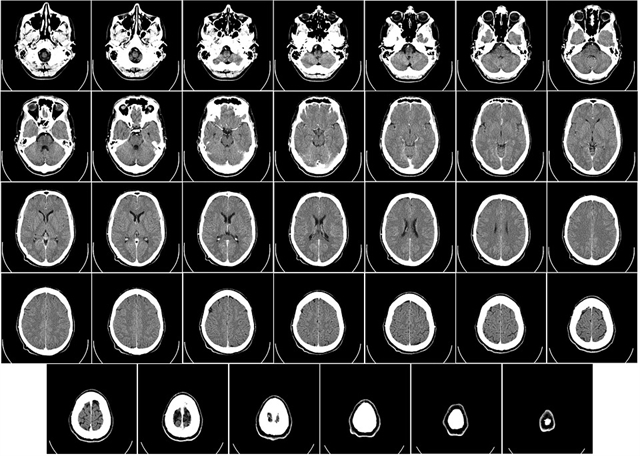

3.1 I primo motivo, relativo alla condotta del C., nella rubrica denuncia violazione e falsa applicazione, ai sensi dell'art. 360 c.p.c., comma 1, n. 3, dell'art. 2043 c.c., art. 1176 c.c., comma 2, artt. 1218 e 2236 c.c. e art. 116 c.p.c.Adduce la ricorrente che la condotta del C. sarebbe stata imprudente e omissiva, violando così l'art. 2043 c.c., art. 1176 c.c., comma 2, e art. 2236 c.c. per avere effettuato l'operazione chirurgica il (OMISSIS) senza accertamento strumentale, utilizzando soltanto la TAC che aveva fatto eseguire la ricorrente stessa il (OMISSIS) (erroneamente qualificata dal giudice d'appello RMN). Inoltre dalla cartella clinica risulterebbe che la massa solida da asportare non era totalmente "incapsulata": pertanto il tumore non fu asportato in misura completa. Si richiamano poi osservazioni del consulente di parte professor G. (che il giudice d'appello rileva non trovarsi agli atti), secondo il quale il chirurgo avrebbe dovuto operare ai fini dell'esame istologico anche prelievi del tessuto osseo. Dalla cartella clinica sarebbe quindi risultata la violazione del dovere di diligenza del C.; e là dove nega tale violazione, il giudice d'appello non rispetterebbe l'art. 116 c.p.c. in riferimento agli artt. 2697 e 2702 c.c. Inoltre, nella prima visita di controllo compiuta dal C. nel (OMISSIS), il chirurgo non fece eseguire analisi strumentali, e si avvalse "con estrema superficialità" di una nuova TAC del (OMISSIS) che ancora una volta si era procurata la B.. Dal referto che da tale TAC aveva tratto fuori il radiologo dottor S. emergevano due dati preoccupanti: un'area di un centimetro "di alterata intensità di segnale" e una "immagine cuneiforme", quest'ultima secondo il radiologo "meritevole di valutazione Rx-grafica". Nonostante ciò, il C. si sarebbe limitato a rinviare la successiva visita di controllo a distanza di un anno.